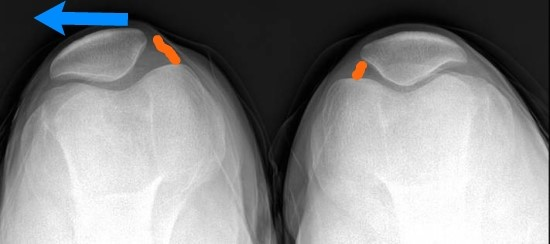

슬개대퇴 통증 증후군의 원인으로는 대퇴사두근 근력의 약화 또는 힘줄의 염증, 연골연화증이나 해부학적 모양의 이상 같은 슬개골 자체의 문제, 무릎 지방패드의 염증, 내측반월판의 병변 등 여러 가지가 있습니다. 저는 무릎을 굽히고 펼 때마다 슬개골이 바깥쪽으로 살짝 빠졌다 들어오는 슬개골 아탈구가 있습니다. 해부학적 구조는 괜찮은 것 같은데, 아마도 지나치게 운동을 안 해서 초래된 대퇴사두근 근력 부족에 의한 것으로 생각됩니다.

슬개대퇴 통증 증후군은 쉽게 치료되지 않는 만성 질환이며 보통은 무릎 양측에 통증이 나타납니다. 여자가 남자보다 골반이 넓고 대퇴에서 무릎으로 이어지는 각도가 커서, 슬개골이 더 많은 힘과 충격을 받기 때문에 여자 환자가 좀 더 많습니다. 오랜 시간 앉아서 일하는 사람에게 많이 나타나며 쪼그려 앉기, 계단 오르내리기, 그리고 바닥에 무릎을 꿇는 동작으로 인하여 유발될 수 있습니다. 달리기는 체중의 3~4배에 달하는 충격이 다리로 전달되기 때문에 무릎 주변의 근육을 긴장시켜 정렬을 망가뜨릴 수 있습니다. 이러한 자세와 동작들이 슬개-대퇴 관절의 염증을 유발하고 압력을 증가시키기 때문에 통증이 발생합니다.